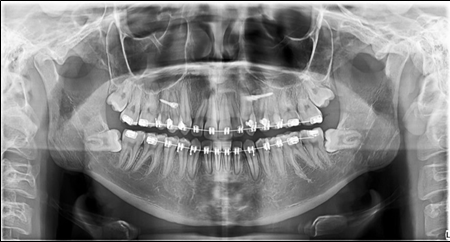

The panoramic radiograph showed bilateral mandibular third molars. The level of alveolar bone crest was within the normal range. (Figure 3)

Figure 3.Pretreatment panoramic X-ray